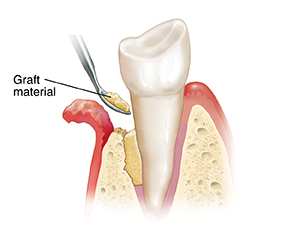

A graft helps your body replace lost bone. The graft consists of your own bone, synthetic material, or bone from a tissue bank. A gel containing growth factors may also be used to stimulate tissues to grow. This is how a graft is done:

Placing the graft. First, a gum flap is created. Growth factors may then be applied to the root. Graft material is packed into the area where bone was lost. This material provides a platform for new bone to grow. In some cases, a membrane may be needed to cover the graft. It may dissolve on its own or may need to be removed after healing.

| Placing the graft. |